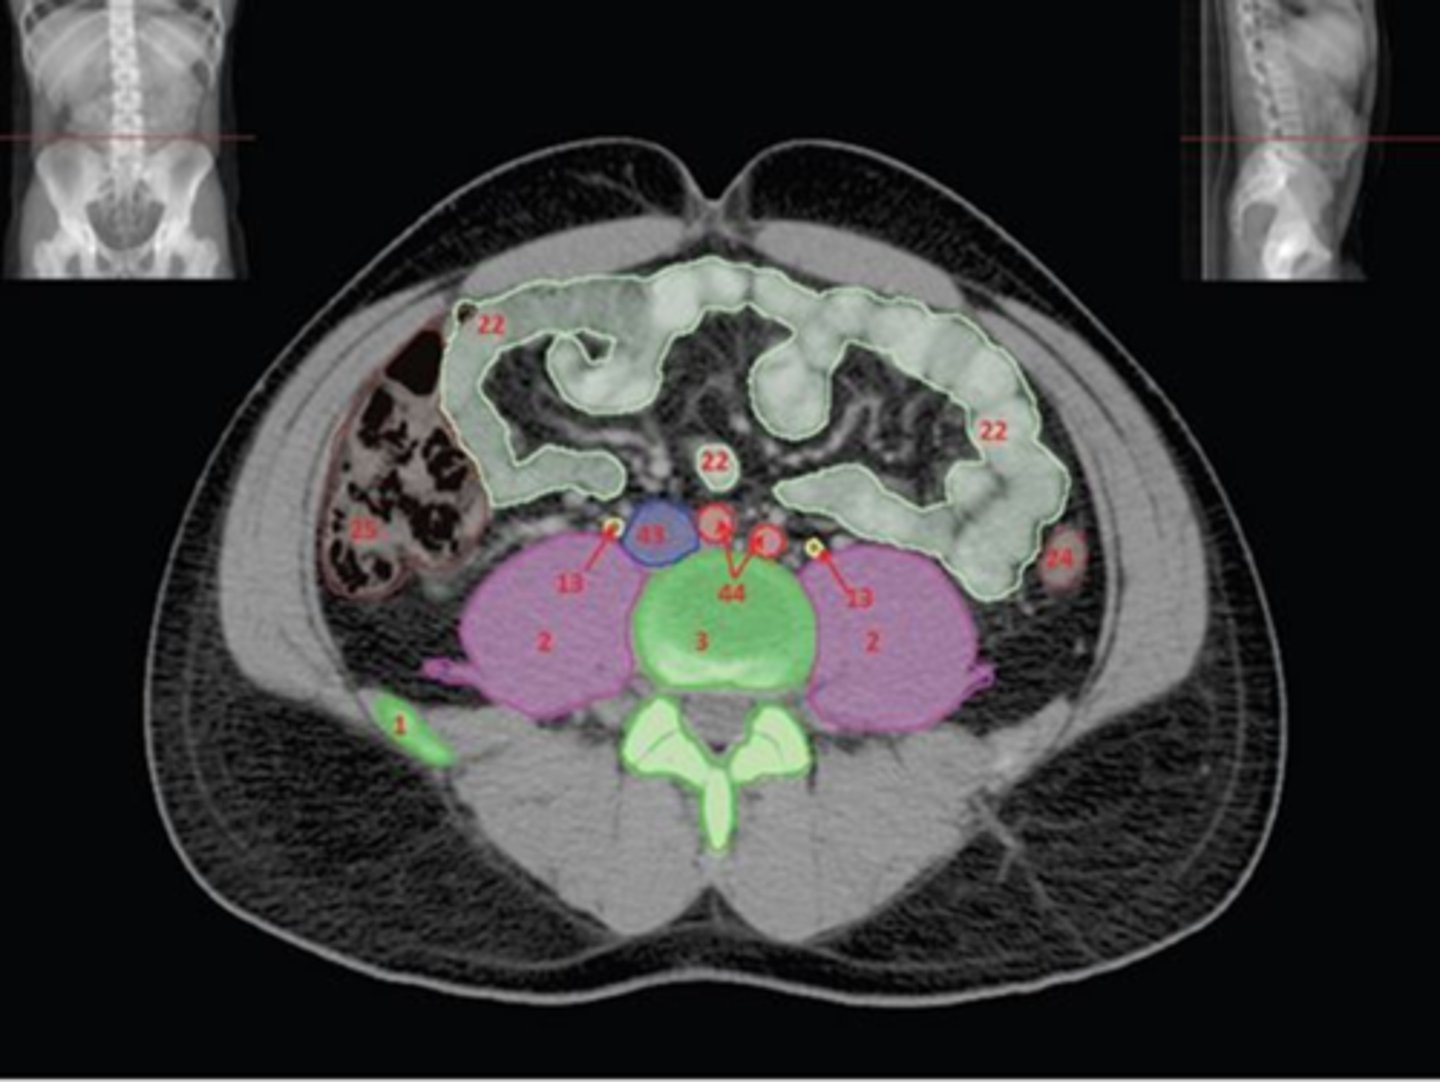

1) SI joint

2) Body

3) Sacral promontory

4) Sacral canal

5) Ilium

6) Lateral mass

7) Articular process

Name all numbered structures

1) Ala of ilium

2) SI joint

3) Sacral promontory

4) Lateral mass of Sacrum

5) Sacrum

Name all numbered structures